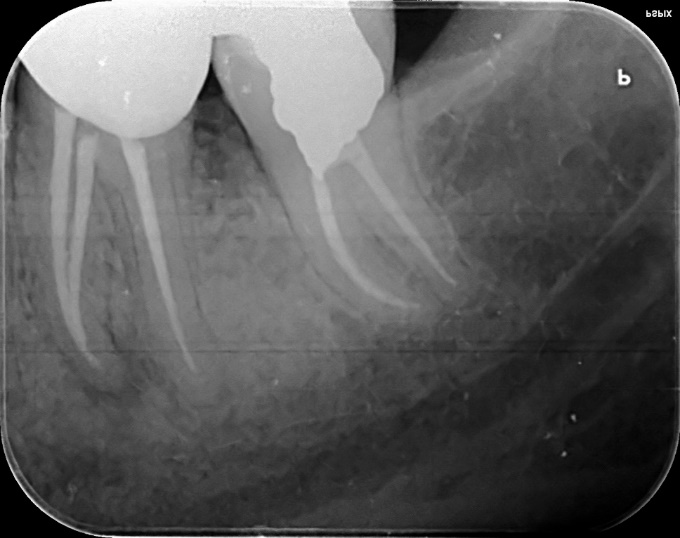

Lower Molar Primary root canal treatment